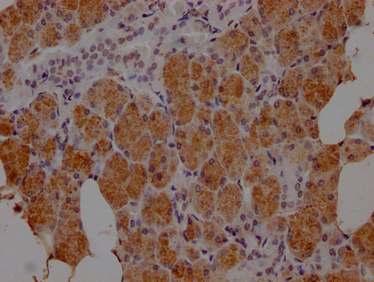

IHC image of PACO64275 diluted at 1:100 and staining in paraffin-embedded human salivary gland tissue performed on a Leica BondTM system. After dewaxing and hydration, antigen retrieval was mediated by high pressure in a citrate buffer (pH 6.0). Section was blocked with 10% normal goat serum 30min at RT. Then primary antibody (1% BSA) was incubated at 4°C overnight. The primary is detected by a Goat anti-rabbit IgG labeled by HRP and visualized using 0.05% DAB.